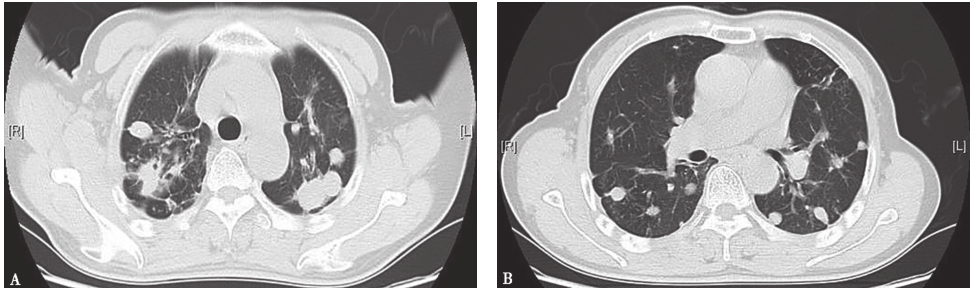

临床确诊后,给予3HRZE/9HRE抗结核治疗,1年后复查胸部CT,示双肺原结节样病灶明显吸收(图8)。

图8 抗结核治疗1年后胸部CT表现